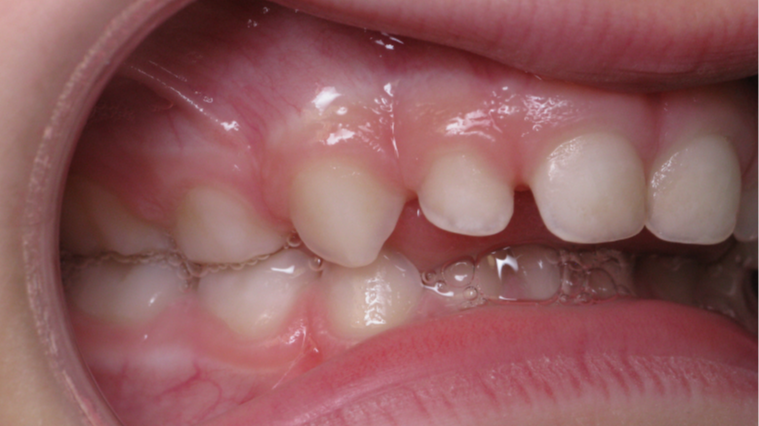

Décalage entre les dents d avant en arrière

appareillage mobile

bilan début fin de traitement